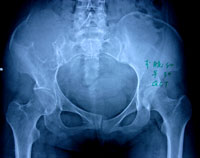

症状主要表现为不同程度的疼痛,可伴有肿胀、活动受限,病程从数周至数月不等,无特异性表现,不易从症状方面与其他骨肿瘤区别。骨巨细胞瘤多为单发病变,常见部位是长骨的骨端,最常见的部位是股骨远瑞、胫骨近端、桡骨远端,也可见于骶骨、胫骨远端、肱骨近端,股骨近端和腓骨近端。偶见于手及足部的小骨、胸腰段的椎体和肋骨。

X线平片 对于骨巨细胞瘤的影像学检查, X 线平片是最具诊断价值的放射学检查手段。骨巨细胞瘤在X 线片上表现为骨端的溶骨性破坏,可侵及干骺端,向关节侧延伸侵及部分或全部邻近关节软骨下的骨皮

质。肿瘤大小与发生病变骨的大小有关。肿瘤延患肢骨长轴侵及的范围往往小于延横轴侵及的范围,在骨干侧可见筛孔样改变,而在骨端的周围可见明显的骨皮质膨胀、变薄。病变内部为不同程度的溶骨改变,皮质外多没有骨膜反应;当出现病理骨折时则可见骨膜反应。通常可见到骨膜下新生骨有中断,骨膜保持完整,病变的松质骨边缘部分可有明显的界限。骨巨细胞瘤没有肿瘤基质的矿物化,关节渗出少见,但经常伴有病理性骨折发生。长骨以外部位的骨巨细胞瘤在X 线片上无特征性表现,与其他溶骨病变没有区别。

X线主要表现为骨端变心位溶骨性破坏而无滑膜反应,病灶骨皮质膨胀变薄,呈肥皂泡样改变。

X线片表现:骨骺处有局限的囊性改变,一般呈溶骨性破坏,也可有“肥皂泡”样改变,其扩展一般为软骨所限。不破入关节,少有骨膜反应,肿瘤范围清楚,初发时病变在骨骺内旁侧,发展后可占骨端的全部,骨皮质膨胀变薄,有的可以穿破,进入软组织。X线片可显示其一般特点,但仍不足以确诊。